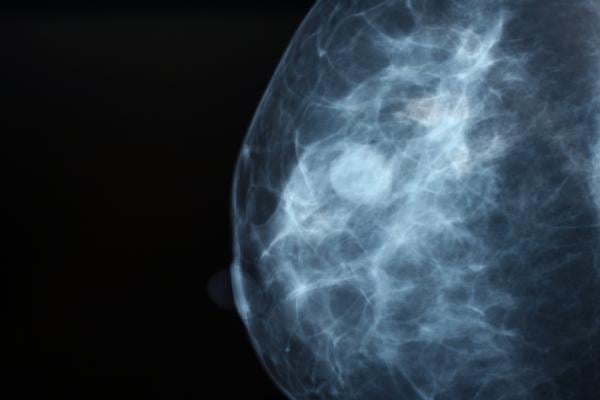

October 24, 2022 — A three-week course of radiation therapy is as safe and effective as four to six weeks of treatment for patients with early-stage breast cancer who have a higher risk of having their tumors recur, results of a randomized phase III clinical trial show. Delivering fewer, but higher, doses of radiation following lumpectomy, while concurrently delivering a radiation boost to the surgical site, led to similar outcomes as a longer course of treatment. Findings of the NRG Oncology/RTOG 1005 trial (NCT01349322) will be presented today at the American Society for Radiation Oncology (ASTRO) Annual Meeting.

The study can help guide treatment decisions for patients who qualify for breast-conserving therapy but face a higher risk of tumor recurrence due to slightly larger tumor size or other factors. Previous studies have shown a three-week course of radiation therapy is as safe and effective as conventional six-week therapy for patients with a low risk of tumor recurrence, but patients who are at higher risk for tumor recurrence need an additional radiation boost to the lumpectomy site.